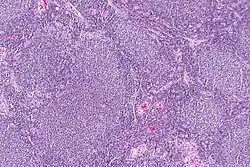

Diffuse B-cell lymphoma | Lymph node FNA specimen showing diffuse large B cell lymphoma. | Category: Histopathology of diffuse large B cell lymphoma | Diffuse large B-cell lymphoma |

Follicular lymphoma | Micrograph showing a small B-cell lymphoma compatible with follicular lymphoma. H&E stain. | Category: Histopathology of follicular lymphoma | Follicular lymphoma |